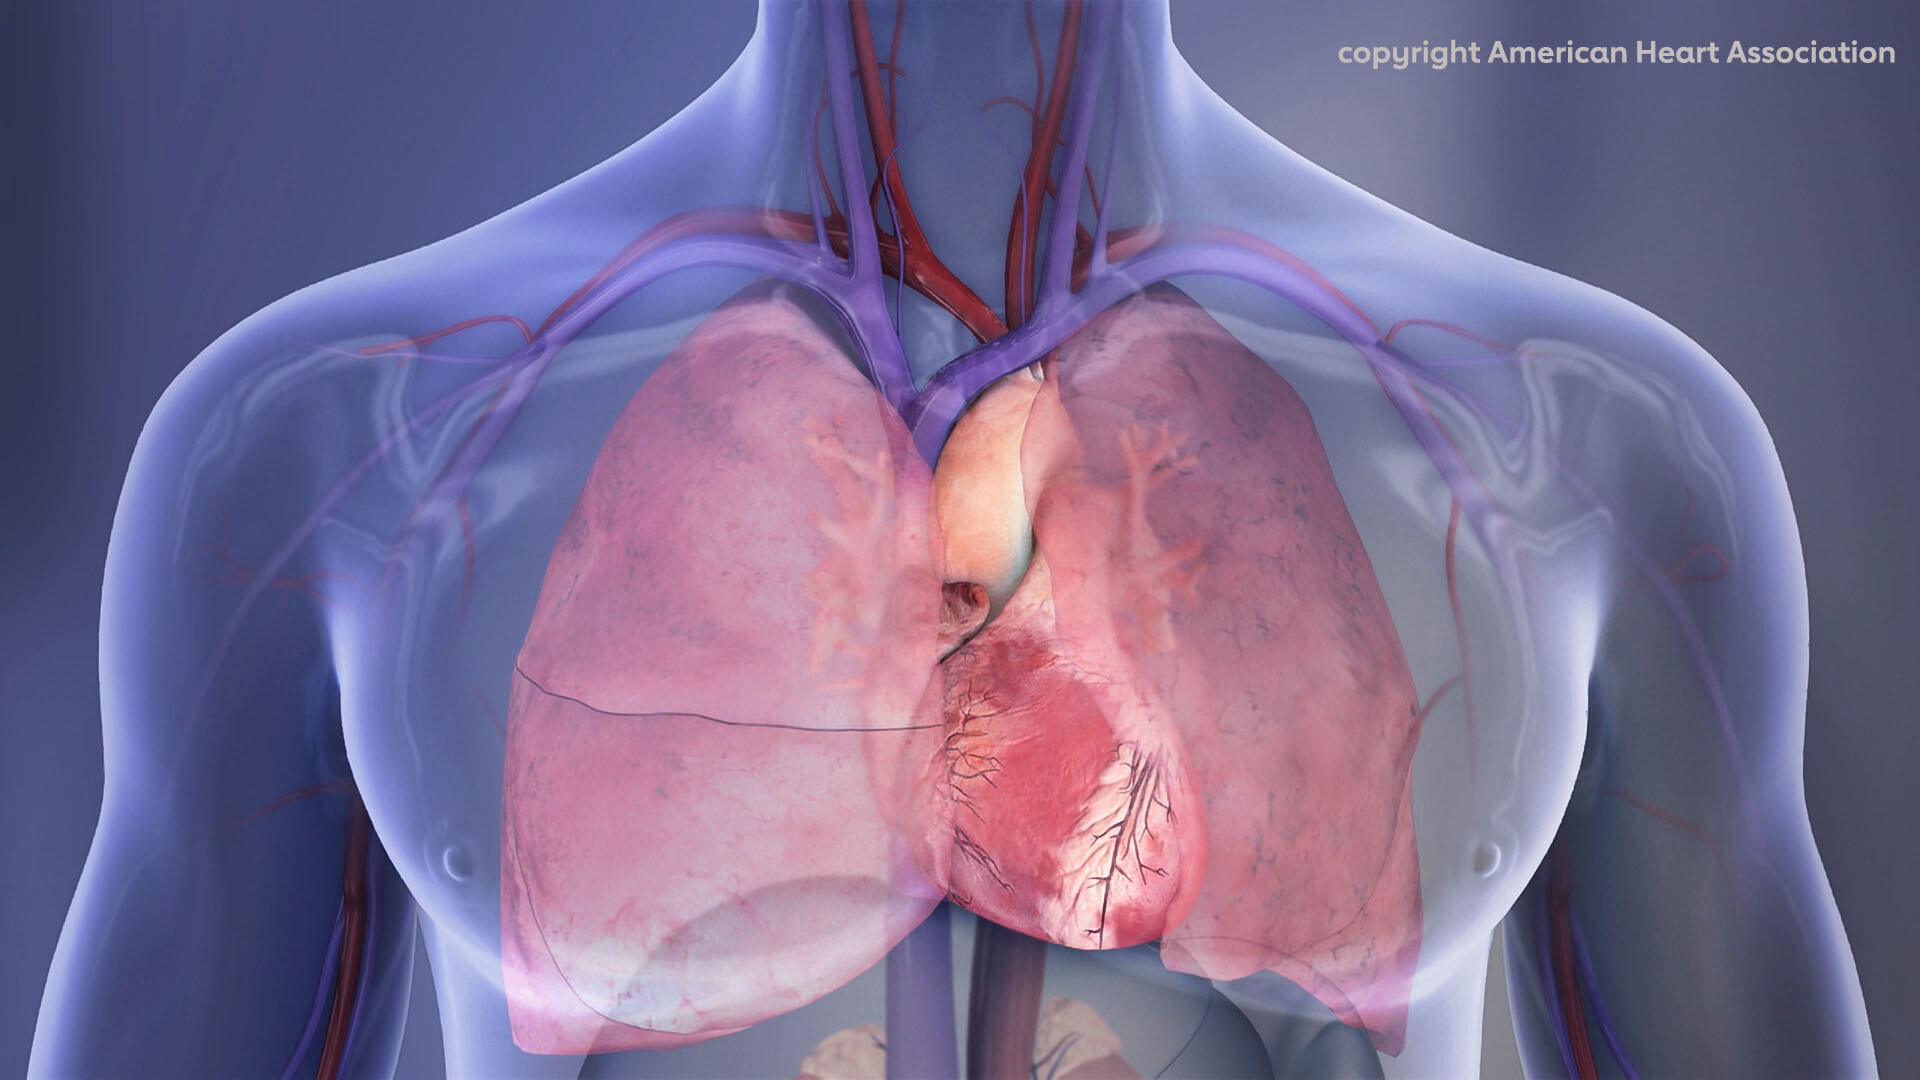

Crédito: Associação Americana do Coração

A embolia pulmonar (EP), um tipo de coágulo sanguíneo nos pulmões, envia mais de meio milhão de pessoas para hospitais dos EUA todos os anos – e mata cerca de um em cada cinco pacientes de alto risco, de acordo com a atualização estatística de 2025 da American Heart Association. A EP é a terceira principal causa de morte cardiovascular nos EUA Embora tenham sido feitos progressos no tratamento da EP, a embolia pulmonar continua subdiagnosticada, subtratada e gerida de forma inconsistente.

EP é um tipo de tromboembolismo venoso (TEV) ou coágulos sanguíneos nas veias. A EP ocorre quando um coágulo sanguíneo se liberta, geralmente de uma veia profunda das pernas, e se aloja nos vasos que irrigam os pulmões. TEV é uma condição potencialmente fatal que contribui para até 100.000 mortes a cada ano nos Estados Unidos. De 2008 a 2018, a mortalidade relacionada com EP aumentou, sublinhando a urgência da intervenção.